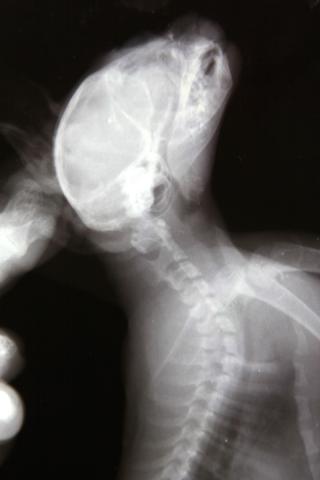

Здравствуйте. У меня приёмный котёнок-подобрашка. Был подобран на улице девушкой волонтёром в первых числах августа, примерно в 2-х месячном возрасте. У котенка расстройства координции. Светлана сделала котёнку рентген, на котором выявлено повреждение 1 шейного позвонка. Первично было назначено: пирацетам, ловетта, фуросемид; далее добавлены мильгамма, преднизолон. Переназначение от другого врача: Мильгама, Нейромедин 0,3*2р/д 15 дней. Курс Нейромедина проведён уже 2-х кратно. Улучшения незначительные, недолговременные. Нарушения координации выражются в треморе головы при малейшем возбуждении (бьётся носом об тарелку, когда кушает), дискоординация движения ног при ходьбе- спина не выпрямляется, задние ноги находят на передние- заваливается на бок, плохо развиты задние конечности, передние контролирует лучше. Планируем в ближайшее время МРТ. Какой отдел нам делать, посоветуйте. Буду рада любой информативной помощи. Спасибо! Это наши снимки.

Извините, как-то пропустила вашу тему. Снимки нечеткие, рассмотреть масштаб трагедии я по ним не могу, тем более снимки сделаны только в сагиттальной проекции, а хотелось бы увидеть и фронтальную.

Tella, Михаил Александрович! Очень благодарна вам за содержательные ответы!!!! Уточню, так как снимки выложены, действительно, не в очень хорошем качестве. Врач, наблюдающий Севу и назначивший нам последнее лечение увидел на снимке трещину на атланте. Где порекомендуете провести нам подобное исследование и возможную операцию? Специализируетесь-ли вы в этом направлении?

Лично я специализируюсь именно на этом направлении. Но про трещину на атланте - как то очень сомнительно. В таком, как у Вас, возрасте кости не ломаются, а, скорее, гнуться. И кости позвонков очень эластичны. Да и трещина если и есть, то что плохого? Трещина - это перелом без смещения. А раз нет смещния то в чем может быть проблема?